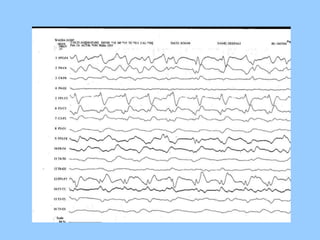

1. The document discusses EEG patterns and findings in various neurological conditions seen in children. It includes descriptions of normal EEG findings as well as abnormal patterns seen in conditions like absence seizures, West syndrome, benign childhood epilepsy with centrotemporal spikes, Lennox-Gastaut syndrome, non-convulsive status epilepticus, subacute sclerosing panencephalitis, and herpes encephalitis.

2. Case studies are presented with clinical histories and EEG findings to illustrate different pathologies. Treatment options are also mentioned for many of the conditions.

![• Station No : A term newborn who required resuscitation at

birth with a 5 minute APGAR of 5 is admitted in NICU. The

neonate had seizures in first 12 hrs of life

• Identify the findings-[1]

• What is the significance of this finding- [1/2]

• Name of the staging system other than Sarnat and Sarnat and

give its component- [1]](https://image.slidesharecdn.com/eeg-141015043102-conversion-gate01/85/Eeg-in-pediatric-DNB-PEDIATRIC-72-320.jpg)